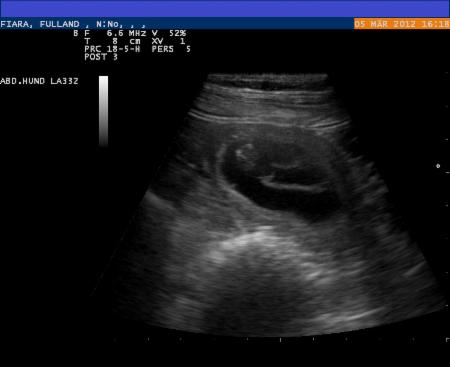

Wir waren am 05.03.2012 beim Ultraschall:

Fiara ist tragend !!!

Und hier die Beweise: Die ersten Fotos der Babys, die Ultraschallbilder !!!

05.03.2012